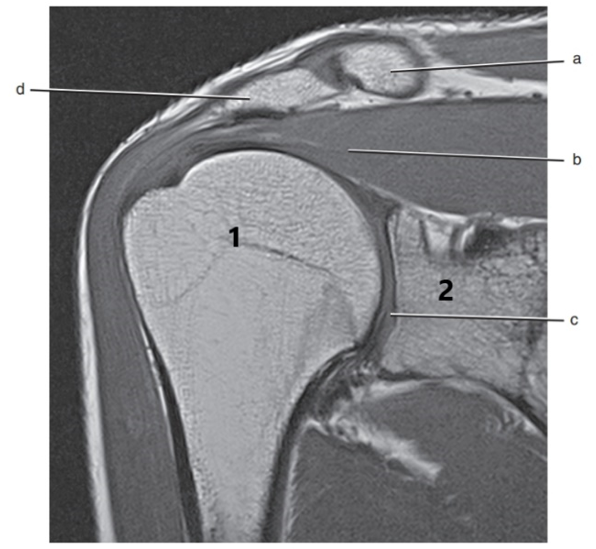

What is # 1 ?

humerus

What is # 2 ?

Acromion Process

What is letter d ?

Acromioclavicular ligament

What is letter b ?

Supraspinatus muscle

Scapular spine